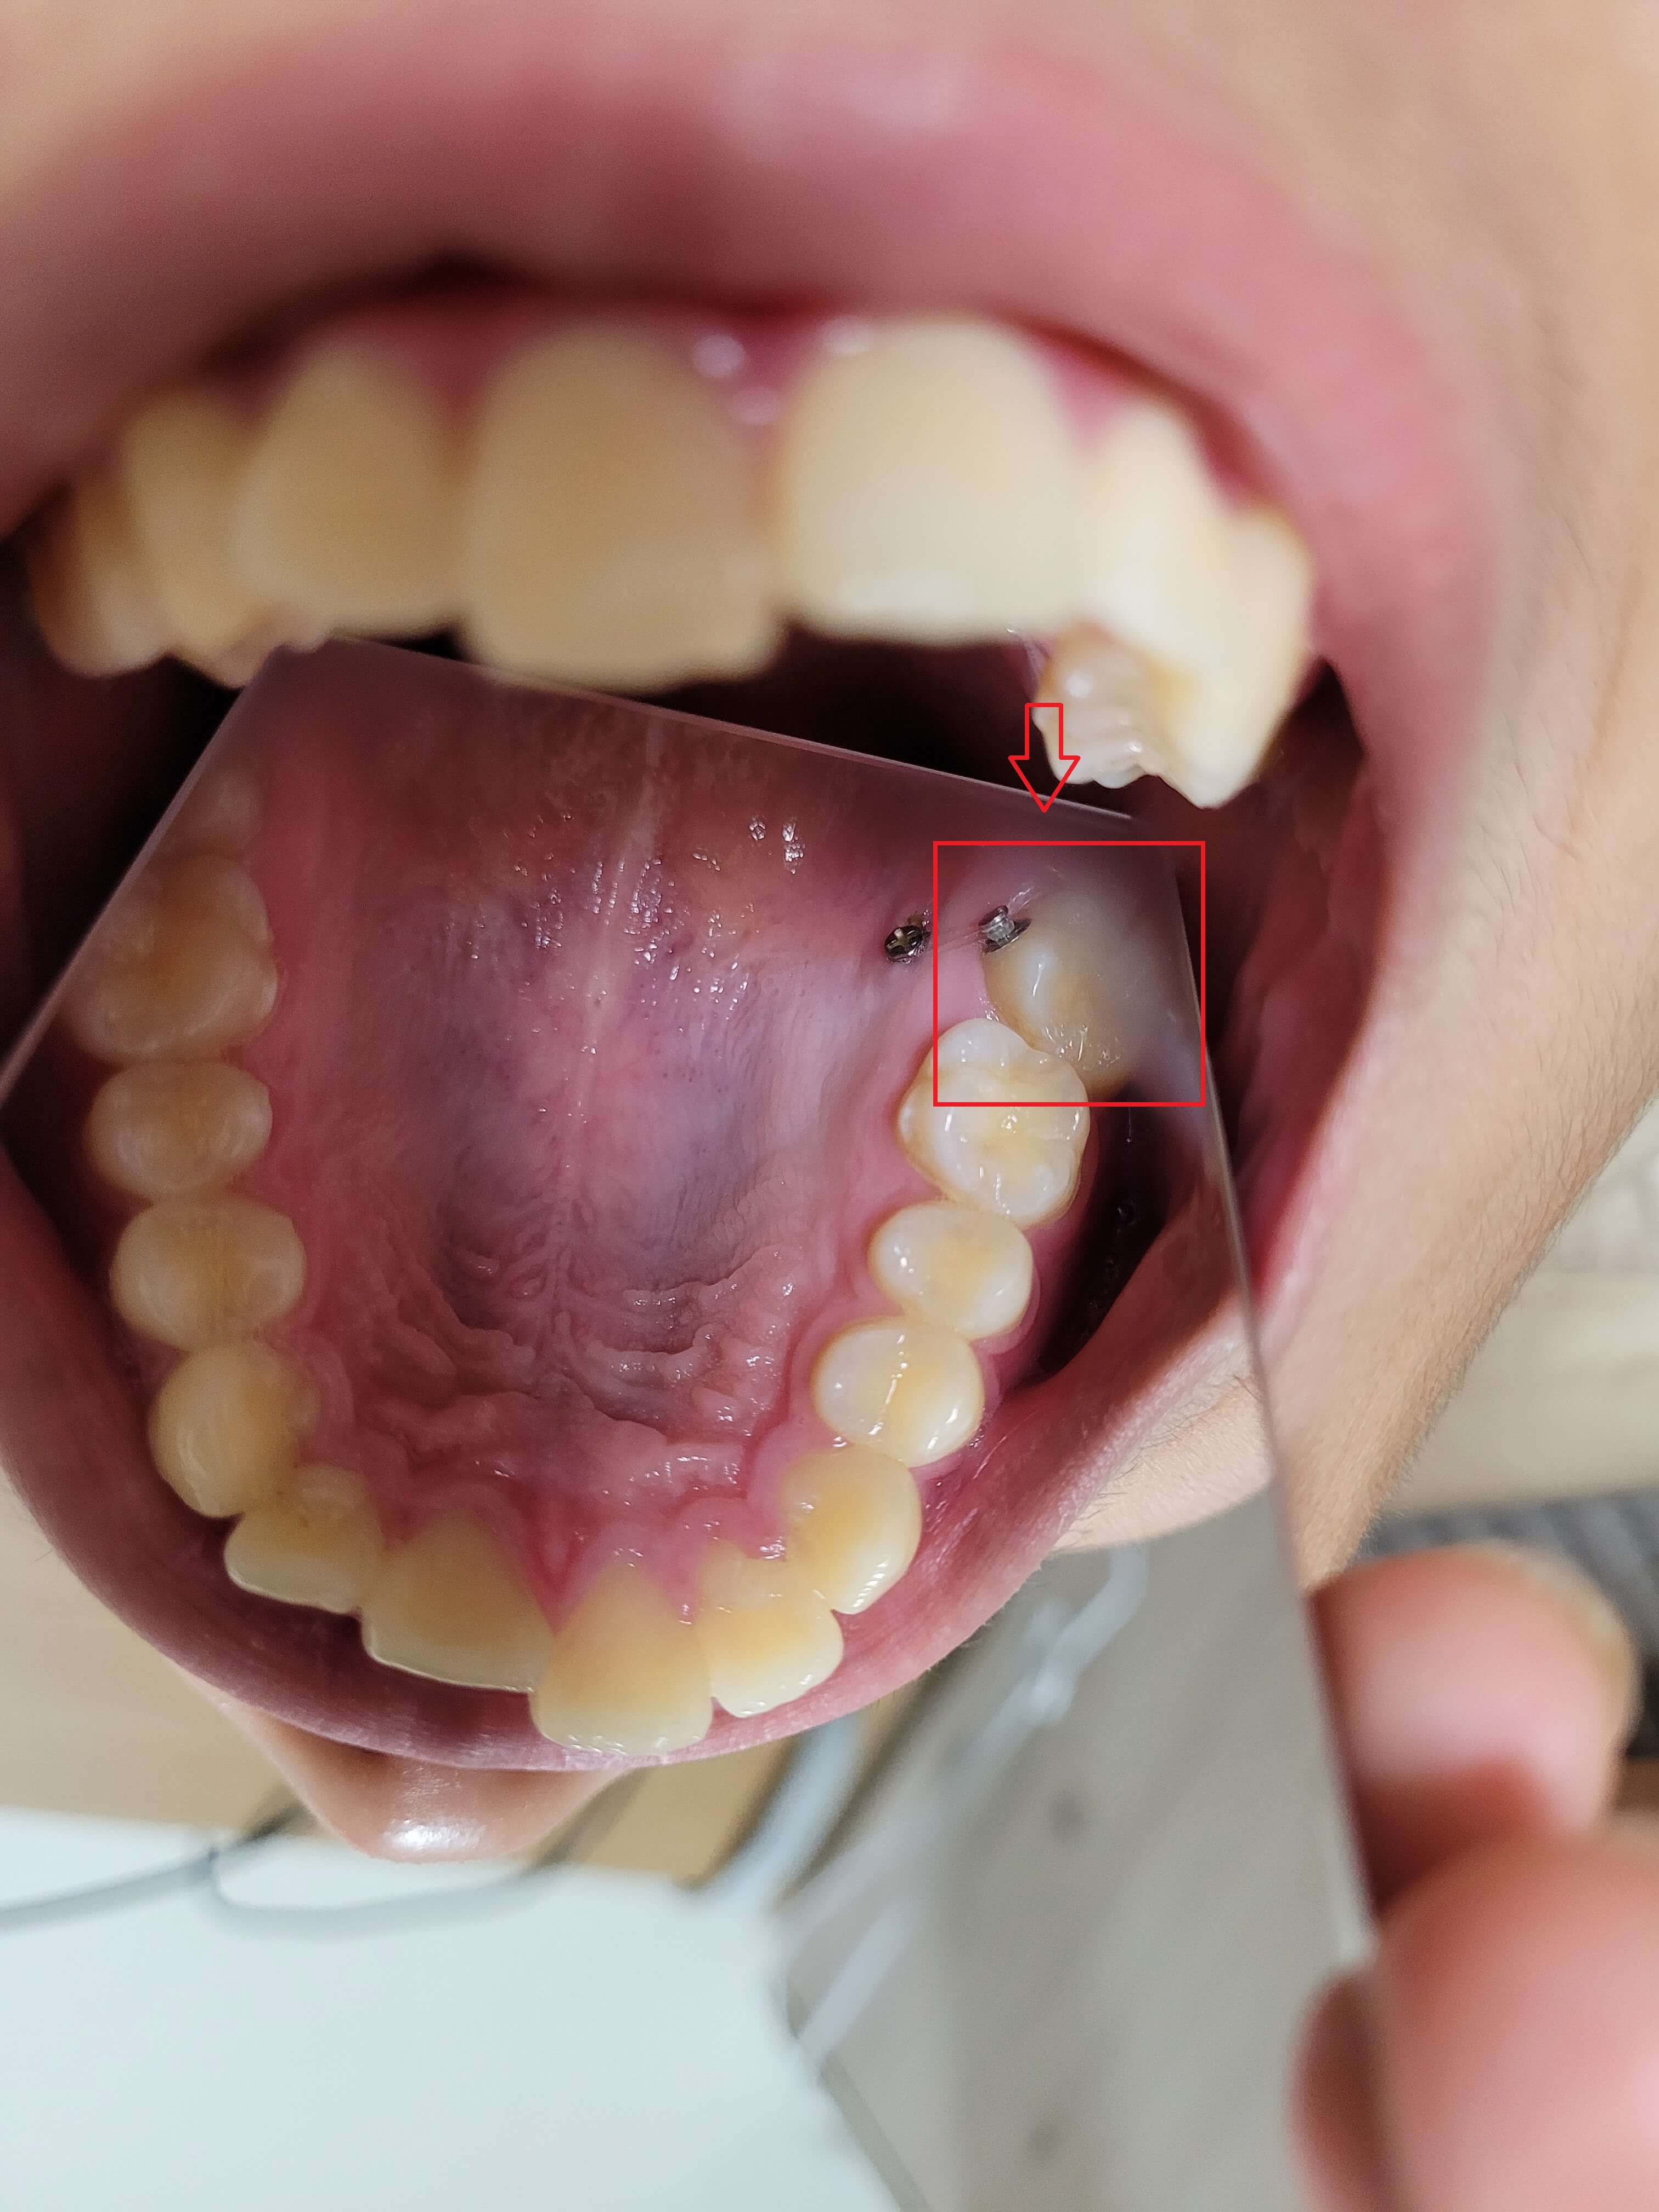

◎ 아들치아교정 전 상태확인 (가위교합사진)

- 「윗 어금니 가위교합 1개」

- 「아래 어금니 가위교합 1개」

저는 치아가 자유로이 움직인다는 것을 처음 알았습니다. 그리고 복원력이 있다는 것도 알게 되었는데요. 사진에서 보듯이 어금니가 옆으로 누워있습니다.

위, 아래 어금니가 모두 그렇는데 아래 어금니는 브라켓 설치로 힘을 주어 잡아당기고 있고 윗 어금니는 스크류를 박고 고무줄(체인)로 잡아당기고 있습니다.

▼ 아래 어금니 블라켓으로 고정후 힘을 주어 당기고 있는 모습

▼ 윗 어금니는 스크루를 박고 체인으로 묶어서 한 단계씩 줄여나가면서 이동시킴.